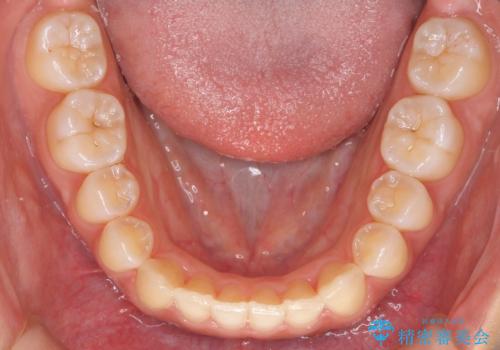

前歯のがたつき インビザラインで 下の奥歯を後ろに下げる

- 上下の前歯のがたつきを主訴に来院。

骨格的に受け口の傾向があり、下の奥歯が前方にに位置しており、下の前歯が特にがたつきが大きい状態でした。

下の奥歯を後ろに下げて下の前歯が前方に出ないように治療しました。

矯正用ミニスクリューを用いて治療しています。

奥歯のかみ合わせの前後的なずれをそのままにして治療すると、前歯が突き上げるような状態になってしまいます。

ただその場で並べるのではなく、症状によっては奥歯を後ろに下げる必要があります。